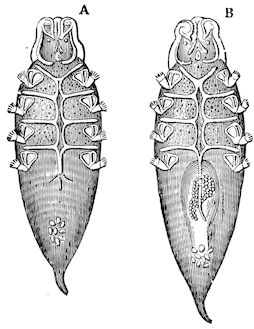

Fig. 3.—Pig suffering from osseous cachexia (fourth stage).

114. The fourth phase, or period of osteomalacia, i.e. softening of the bones, is also the last. It is rarely seen in large animals like horses and oxen, because accidents so often accompany the preceding stages and necessitate slaughter; but it is common in goats and pigs.

In this phase the bones become elastic, soft and depressible, yielding to the pressure of the operator’s fingers.

Fig. 4.—Deformity of the face in the horse shown in Fig. 2.

The flat bones are particularly liable to this change, which is common to domesticated animals. The bones of the head are the first to suffer; later those of the pelvis. The lower jaw becomes swollen, particularly about the centre of the branches which may attain three, four, or five times, their normal thickness.

The depression in the submaxillary space disappears. The upper jaw undergoes similar changes, becoming deformed and thickened until the cavities of the sinuses and the hollow appearance of the palate are lost, while the face is so changed that it cannot be recognised as that of a horse, goat, etc.

The molar teeth are almost buried, their tables alone being visible at the bottom of a depression, the edges of which rise above the neighbouring parts (pig).

Mastication is clearly impossible, the jaws appear paralysed, the muscles powerless, and only swallowing is possible, a fact which explains why life is only prolonged to this stage in animals which can be fed with a spoon or bottle (pigs and goats). The bones of the cranium, although greatly changed in texture, are always less deformed than those of the face.

The changes are such that it is often easy with a mere post-mortem knife to cut the head completely in two. Osseous tissue, properly so-called, has disappeared.

All the constituent tissues, with the exception of the skin and muscles, i.e., the bone, periosteum and aponeuroses, have the appearance and consistence on section of the fibro-lardaceous tissue seen in chronic inflammation.

Fig. 5.—Head of a pig suffering from osseous cachexia.

In the goat, the disease shows some slight peculiarities. Thus, in the second phase, during which goats and sheep suffer so markedly from lameness and pain in the bones, goats often walk on the knees. The disease, however, is uncommon in these animals. The phase of osteoclastia is also less marked and fractures are rare, because the animals weigh less and also because they are less exposed to falls and violent shocks. The bones, nevertheless, are extremely fragile and fractures may be produced at will.

Osteomalacia, on the other hand, is always well marked.

Regarding the development of the disease in pigs, we may repeat what has just been said respecting the goat. Walking on the knees is often one of the first signs, fractures are somewhat rare, and the period of softening and deformity is always very noticeable.

Fig. 7.—Osseous cachexia: softening of the maxillæ.

Fig. 8.—Transverse section through the middle region of the face in a pig suffering from osseous cachexia.

18In the final stages, the bones may be cut with a knife, and a time arrives when bony tissue seems completely to have disappeared; thus, as shown in Fig. 8 herewith, it was possible to cut the entire head of a pig into thin slices without the slightest difficulty. All parts of the head had been affected by the softening change.

From the chemical point of view, the diminution in mineral salts and in phosphate of calcium has long been recognised, but the degree of this change varies according to the phase. In human beings the proportions have been estimated as follows: Normal bone, 50 to 80 per cent. of phosphate of calcium; bone in persons suffering from osteomalacia, 5 to 20 per cent. of phosphate of calcium. The changes in the ossein have not been carefully studied. We only know that histologically the ossein becomes fibrillar, and that chemically it no longer retains its normal composition.